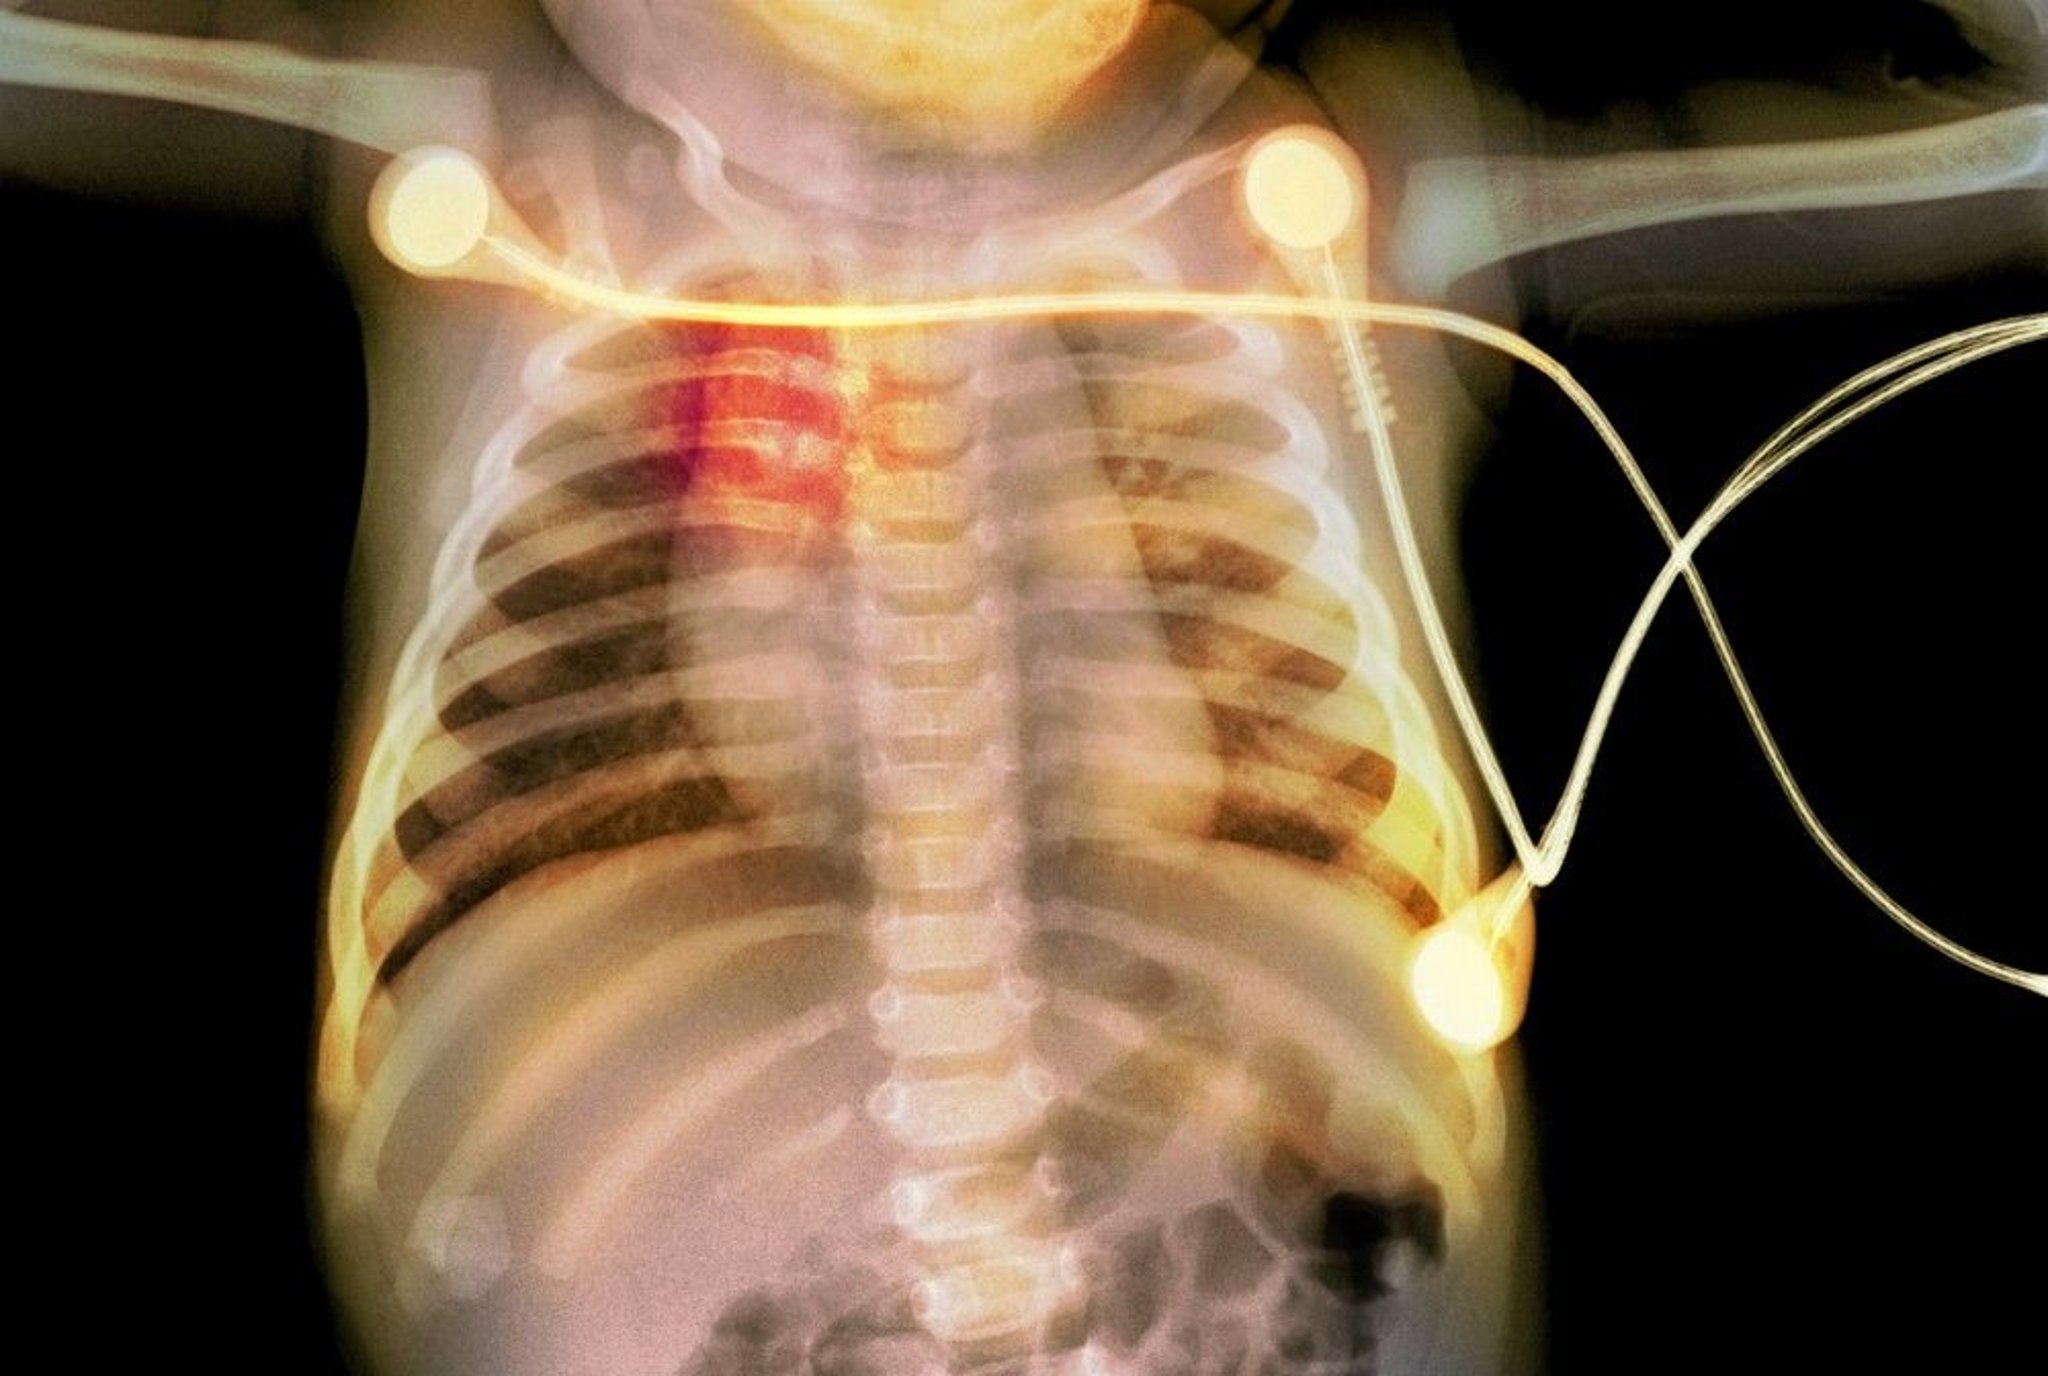

Fraktur Rusuk pada Bayi

Sinar-x ini menunjukkan fraktur tulang rusuk (disorot merah) pada bayi, yang menunjukkan adanya kekerasan pada anak.

PHOTOSTOCK-ISRAEL/PERPUSTAKAAN FOTO SAINS